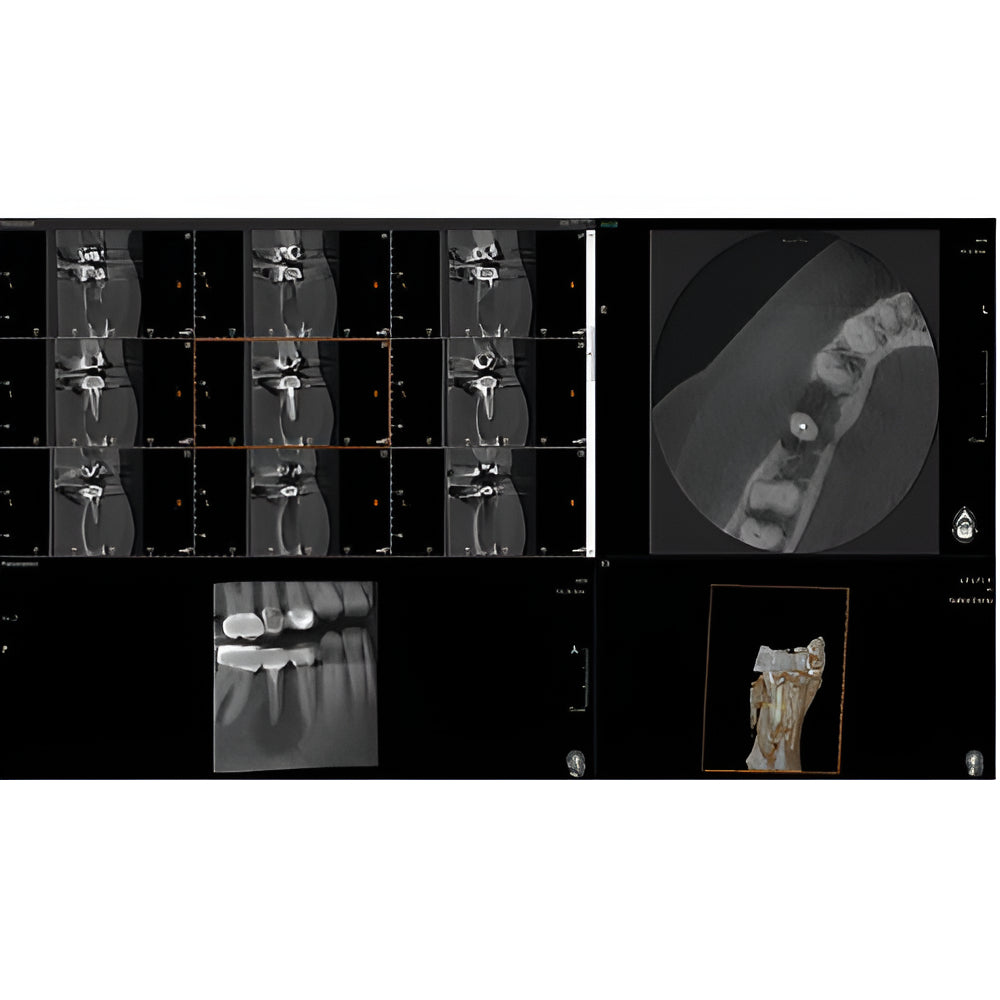

The Vatech PaX-i3D Green panoramic plus cone beam system delivers large field of view (up to 15 x 15 cm) dental CBCT scans in addition to standard 2D panorex and extraoral bitewing X-ray images. This Vatech CBCT machine features the innovative green CT technology which minimizes patient dose, while the Rapid Scan feature delivers high-quality 3D cone beam scans in just 5.9 seconds. A quick exposure time helps to minimize artifacts and motion, while at the same time reducing patient dose, making your imaging process more efficient and safer.

- EZ3Di Imaging Software with License

- 3D Cone Beam

- Multi-FOV

- Focused FOV

- Bitewing Program